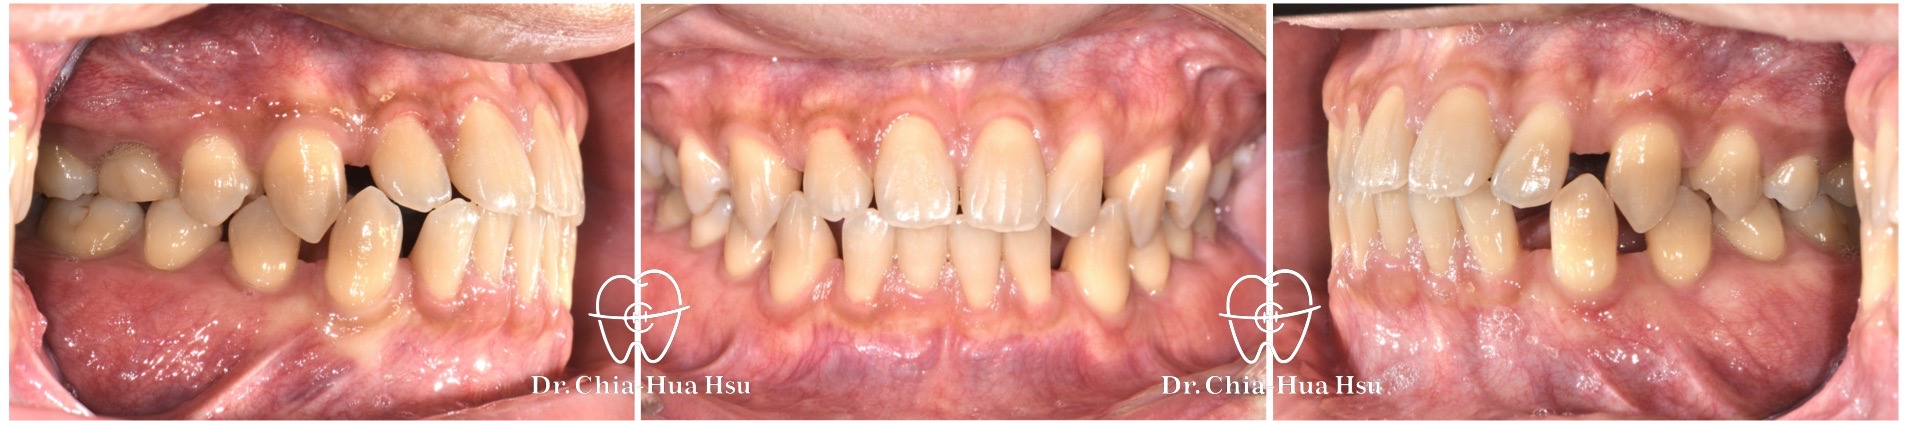

• 病患主訴:牙齒縫隙很多、想改善牙齒排列。

• 問題分析:患者有許多齒間縫隙、先天性缺牙 (右上第二小臼齒、左下第二大臼齒),還有右上第二乳臼齒滯留伴隨牙齒骨性沾黏 (Ankylosis)。

• 治療結果:齒列排齊、縫隙關閉,咬合功能也改善許多。

治療前

治療後